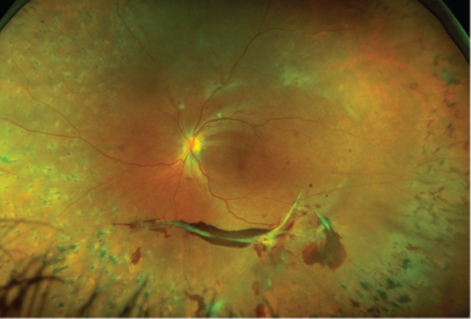

როდესაც დიაბეტური რეტინოპათიის მქონე პაციენტებს LTFU პრობლემები აქვთ, იზრდება დაავადების პროგრესირების ან მხედველობისთვის სახიფათო გართულებების რისკი, PDR შემთხვევაში, ეს შეიძლება ნიშნავდეს, რომ ნეოვასკულარიზაცია ან ფიბროვასკულარული პროლიფერაცია უარესდება და იწვევს სისხლჩაქცევას მინისებრ სხეულში, ნეოვასკულარულ გლაუკომას ან ბადურის ტრაქციულ ჩამოცლას (სურათები 1 და 2).

სურათი 1. 58 წლის ქალი დიაბეტით, რომელმაც მკურნალობა შეწყვიტა (LTFU) 4 წლის განმავლობაში. როდესაც ის კლინიკაში დაბრუნდა, მას აღენიშნებოდა პროლიფერაციული დიაბეტური რეტინოპათია ორივე თვალზე. მარჯვენა თვალზე აღინიშნება ტრაქცია და სრული მაკულარული ხვრელი (A) და ბადურის ტრაქციული ჩამოცლა მარცხენა თვალზე (B).

სურათი 2. 32 წლის ქალს, პროლიფერაციული დიაბეტური რეტინოპათიით, ჰქონდა სისხლჩაქცევა მინისებრ სხეულში. (A). მან მკურნალობა შეწყვიტა 6 თვის განმავლობაში და საბოლოოდ, დაბრუნდა გაუარესებული ტრაქციით და მინისებრ სხეულში სისხლჩაქცევით